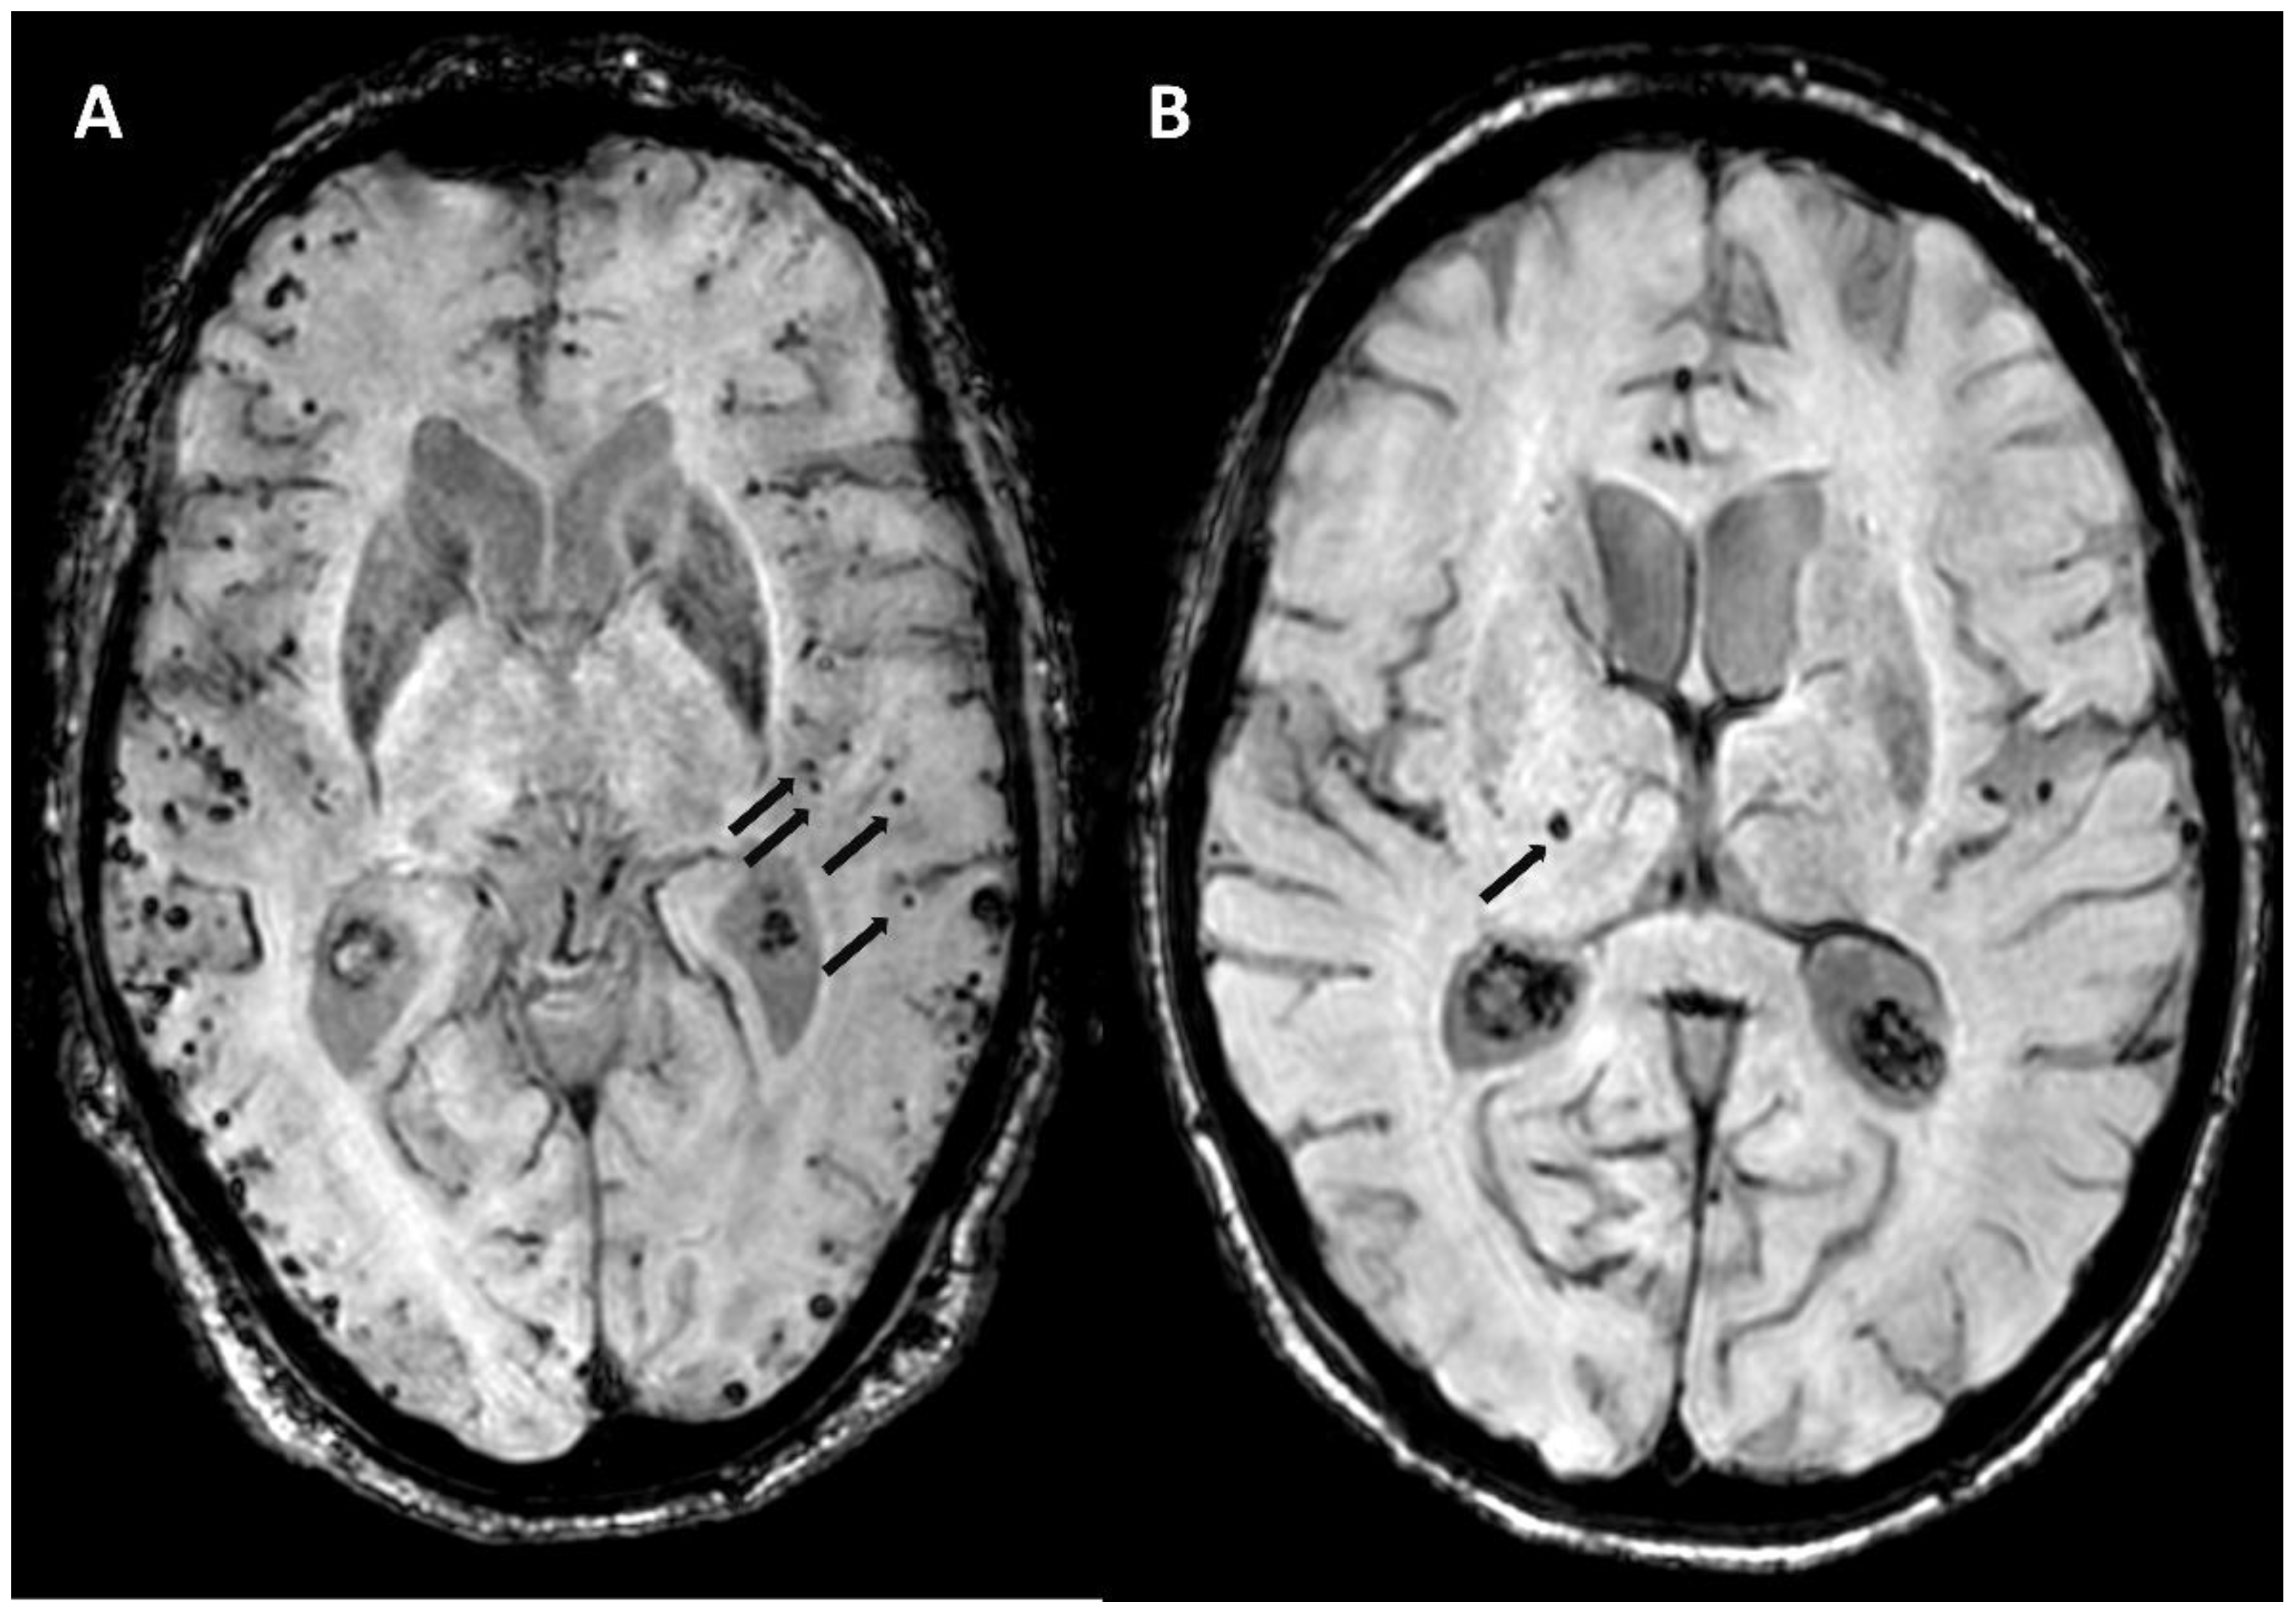

5.1.2. Multiple Cerebral Microbleeds

6.6. Cortical Calcifications

- Koemans, E.A.; Voigt, S.; Rasing, I.; van Harten, T.W.; Jolink, W.M.T.; Schreuder, F.H.B.M.; van Zwet, E.W.; van Buchem, M.A.; van Osch, M.J.P.; Terwindt, G.M.; et al. Cerebellar Superficial Siderosis in Cerebral Amyloid Angiopathy. Stroke 2022, 53, 552–557. [Google Scholar] [CrossRef]

- Rasing, I.; Voigt, S.; Koemans, E.A.; van Zwet, E.; de Kruijff, P.C.; van Harten, T.W.; van Etten, E.S.; van Rooden, S.; van der Weerd, L.; van Buchem, M.A.; et al. Occipital Cortical Calcifications in Cerebral Amyloid Angiopathy. Stroke 2021, 52, 1851–1855. [Google Scholar] [CrossRef]